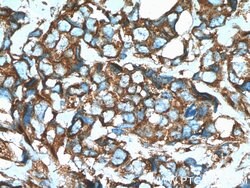

| Western Blot, Immunohistochemistry (Paraffin) | |